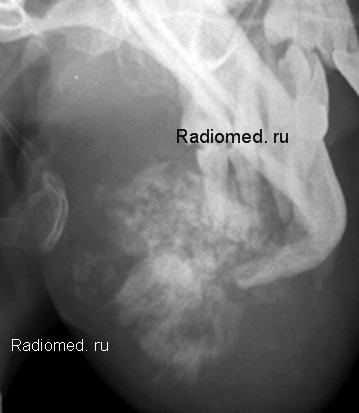

Предлагаются следующие варианты ответов.

1.Тератома.

2.Остеомиелит.

3.Лучевой некроз.

4.Остеосаркома.

5.Литическая форма гигантоклеточной опухоли.

6.Амелобластома.

7.Хондросаркома.

Валентин Львович, интересное наблюдение и очень интересный диф.диагностический ряд- кончно, нужна гистология( как всегда... и во все времена), но наиболее вероятна( в моём понимании) позиция №7.

Гистология есть, иначе-бы не выставляли в качестве "Теста". Есть несколько очень интересных случаев, которые выставим в виде тестов, а затем в соответствующий "набор изображений. Я примерно думал тоже, как Вы, но - это "оказалось рядом", но не в точку.

Я отобрала два диагноза - остеосаркома и хондросаркома.

Делаю ставку на "хондросаркому"

Остеосаркома.

склоняюсь к хондросаркоме.